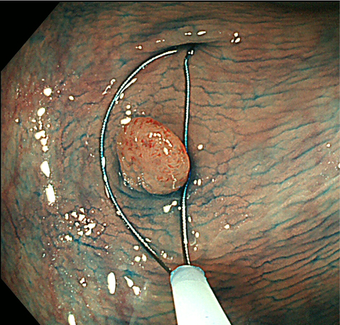

2)内視鏡的粘膜切除術(EMR)

大腸にできた小さな腫瘍やポリープが平坦または陥凹した形の場合、ポリープにスネアが掛かりにくいため、粘膜下に生理食塩水などを注入して隆起させ切除します。切除する病変の大きさや形状によりますが、1日から数日間の入院が必要です。